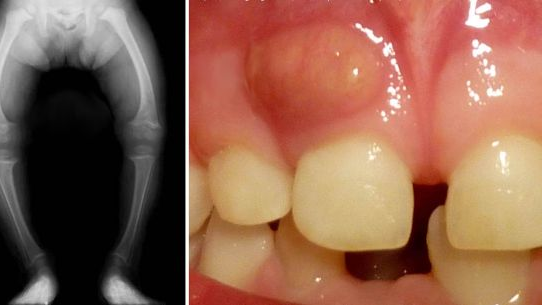

Selon les chercheurs, l'hypophosphatémie liée à X (XLH) est la forme la plus courante de rachitisme héréditaire. Diagnostiquée chez des enfants en bas âge souffrant d´une carence en vitamine D, cette maladie osseuse rare se manifeste par une déformation des os et par l´apparition d´abcès dentaires. Des études antérieures ont démontré que XLH est principalement due à une mutation du gène PHEX codant pour une métallo-protéase au zinc, l’enzyme déficiente entraînant alors une perte de phosphate dans l'organisme occasionnant pas ce fait une déminéralisation des os.

D´après cette nouvelle étude, d'autres facteurs que le phosphate pourraient contribuer à la XLH. En effet, les chercheurs ont constaté que l’activité enzymatique PHEX conduit à une dégradation complète de l'ostéopontine, une protéine majeure pour la restructuration du substrat dentaire et osseux . Le défaut de l’enzyme PHEX perturberait la balance en ostéopontine de l’organisme et empêcherait le durcissement des os et des dents, conduisant aux pathologies telles que les abcès dentaires et les jambes arquées observées chez les patients atteints de XLH.